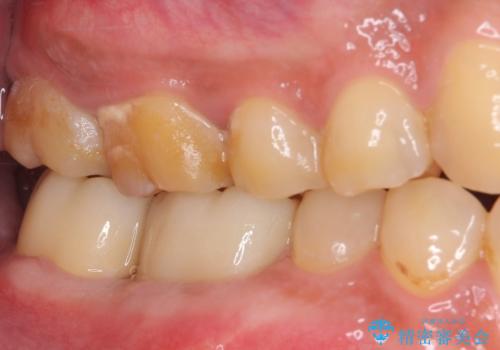

外科処置後の経過を待って、フルジルコニアクラウンにて補綴することとしました。

通っていた歯科医院では、抜歯の可能性が高いと言われていたようですが、何とか健全な状態で歯を保存することができました。